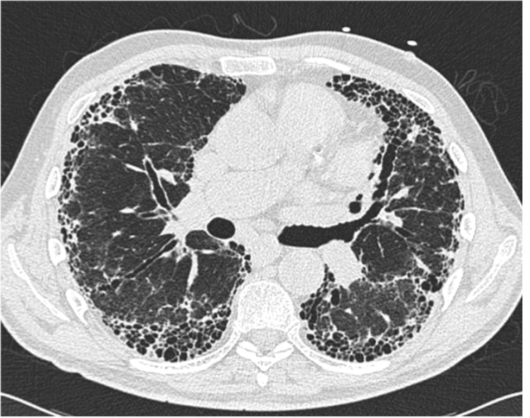

Is this UIP?

This is not UIP because there too much ground glass (too hazy)